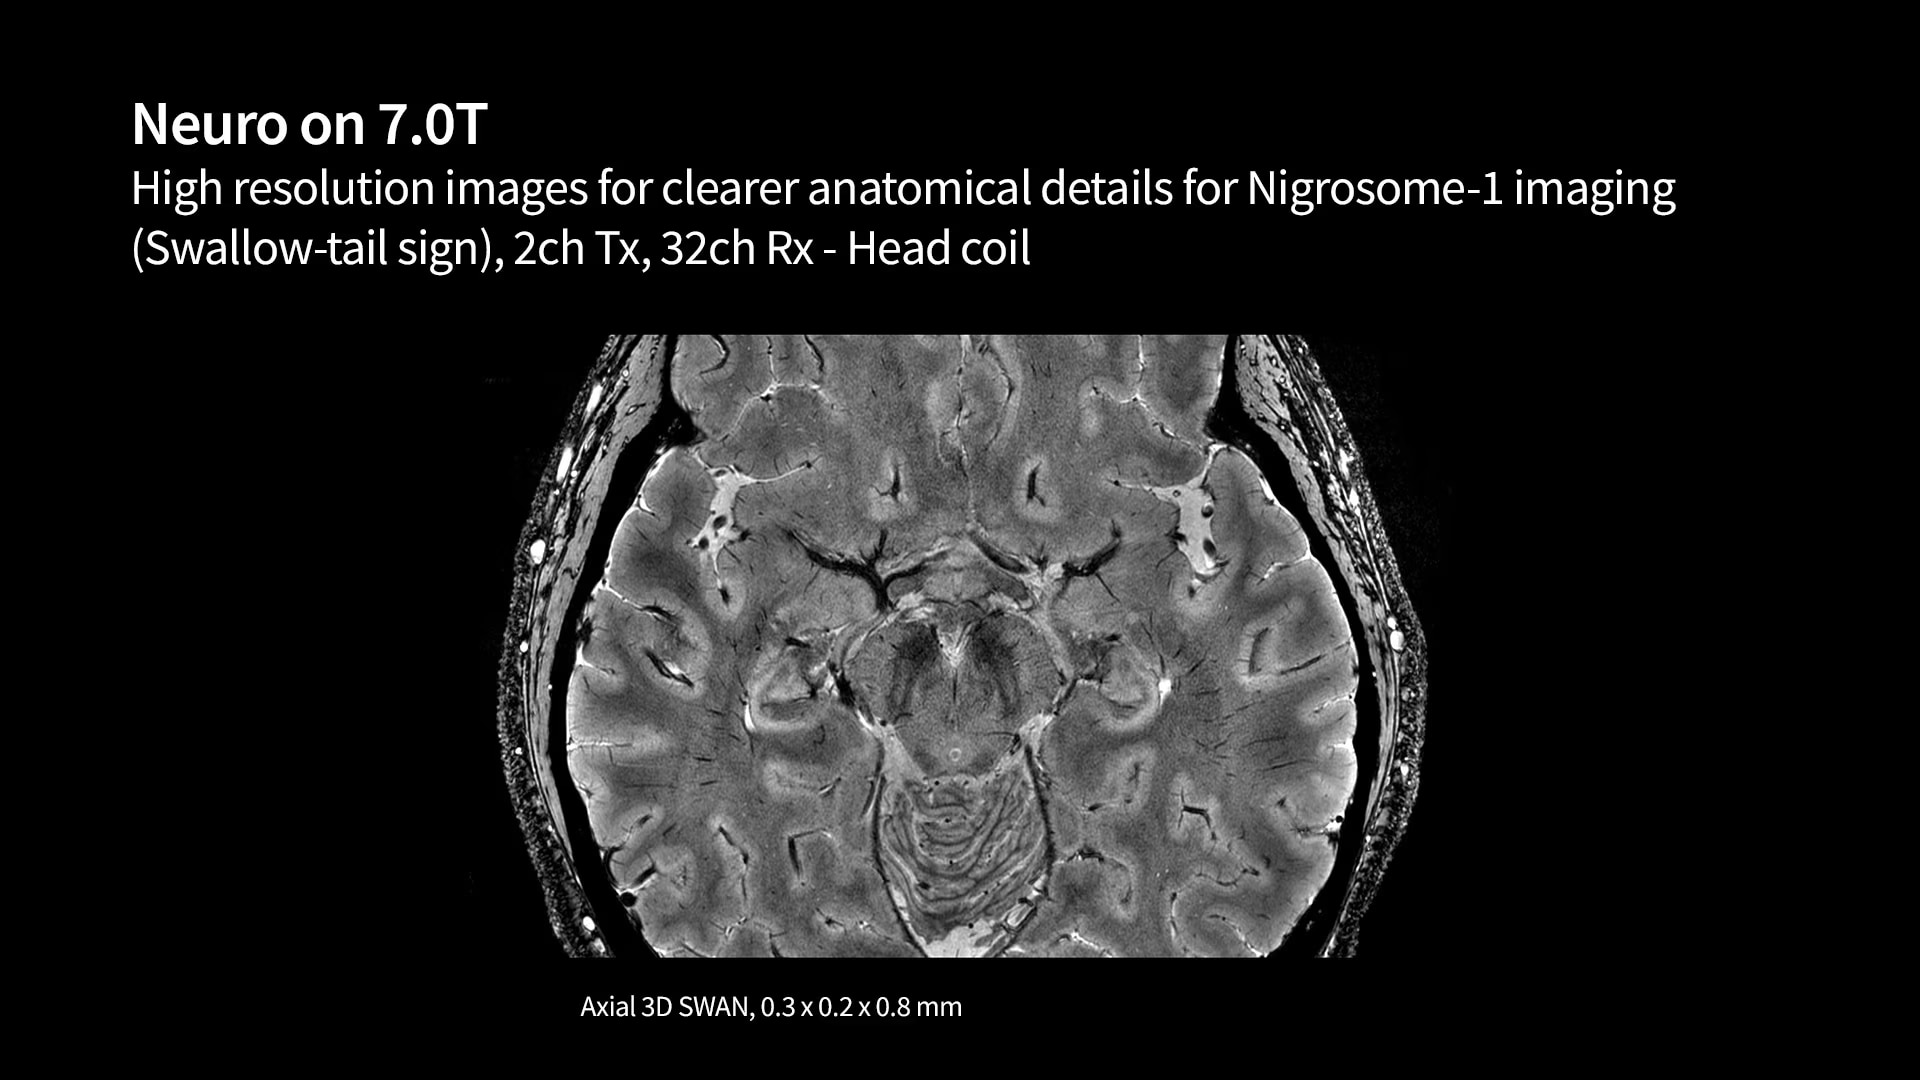

We are helping enable groundbreaking discoveries with a wide array of research-focused MR technology. This technology is opening up research and new care pathways to better understand the world's most debilitating diseases like cancer, as well as neurodegenerative, cardiovascular and psychological diseases. We hope to empower you with ongoing partnerships and continued AI innovation to discover new biomarkers that could lead to significant breakthroughs in your understanding of disease.